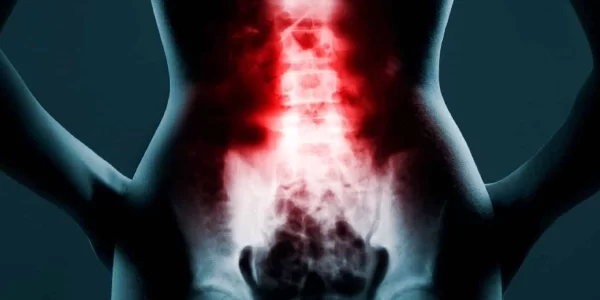

O cisto sinovial se caracteriza por uma bolsa preenchida com liquido e que se desenvolve diretamente nas articulações da coluna vertebral, na maioria das vezes na região lombar. O cisto é uma lesão benigna e de diagnóstico comum em consultórios. Apesar de sua benignidade, esse cisto pode incapacitar o paciente e deixá-lo com limitações motoras por conta das dores desconfortáveis que tendem a aumentar com o tempo, quando não são tratadas adequadamente.

Na maior parte dos casos, o cisto sinovial se desenvolve em articulações do joelho, mãos e pés. Se o cisto se desenvolver na coluna, as dores são ainda mais intensas, pois há a compressão de nervos. É importante destacar que o cisto sinovial não se confunde com o cisto de Tarlov. Enquanto o cisto sinovial é preenchido com liquido sinovial, que é um lubrificante natural das articulações, o cisto de Tarlov é preenchido com líquido cefalorraquidiano (ou líquor), que é um fluido localizado na medula espinhal e no cérebro.

Na maioria das vezes o paciente descobre o diagnóstico de cisto sinovial por sentir uma dor na coluna intensa e buscar ajuda médica. O mesmo vale para outras articulações do corpo, do qual a investigação clinica começa após o paciente se queixar de dores fortes nos joelhos, mãos ou pés.

- Lombalgia intensa.